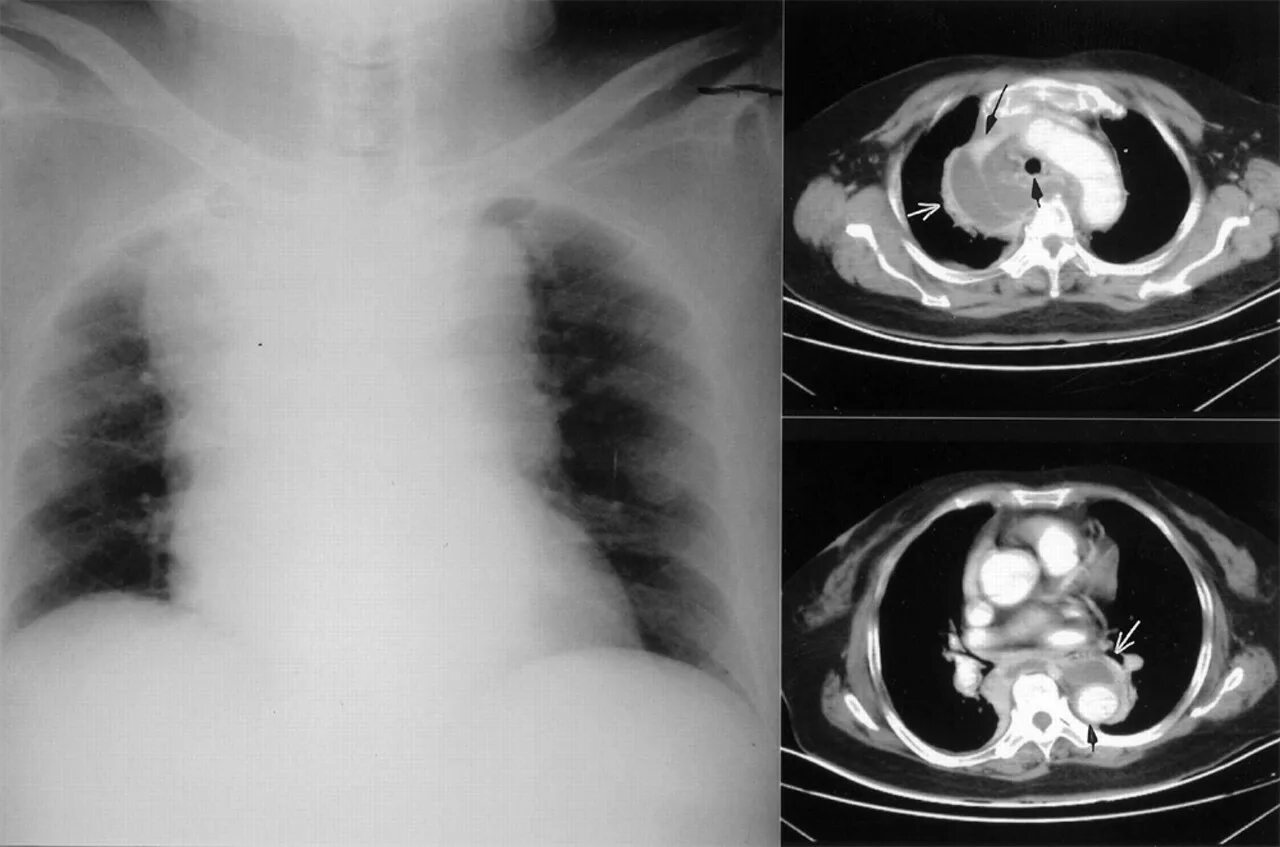

Медиастинит причины